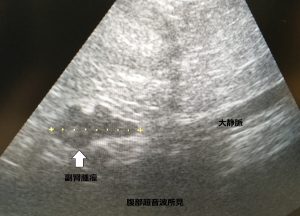

腹部超音波検査を行い、左副腎が通常の1、5倍の大きさで不整な形になっているのを、偶然確認しました。ワンちゃんはとってもお元気です。

褐色 細胞腫は、副腎髄質のクロム親和性細胞から発生して、過剰にカテコールアミン(ノルアドレナリン、アドレナリン)を放出して、高血圧を起こしたり、今回みたいに、偶然 腹部超音波検査で発見して確認されることが多い腫瘍です。腹部臓器に転移したり、大静脈に腫瘍が進行します。以前に、高血圧が原因と思われる眼底出血、痙攣を起こしたワンチャンが来院して、同じ腫瘍を診断したこともあります。